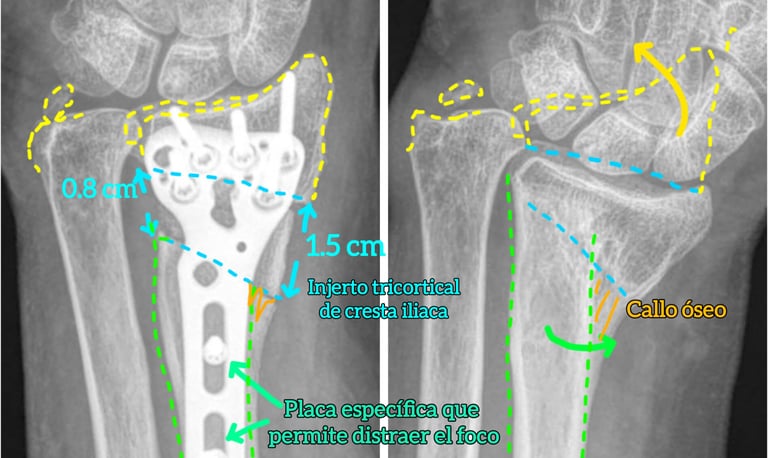

Pseudoartrosis de escafoides